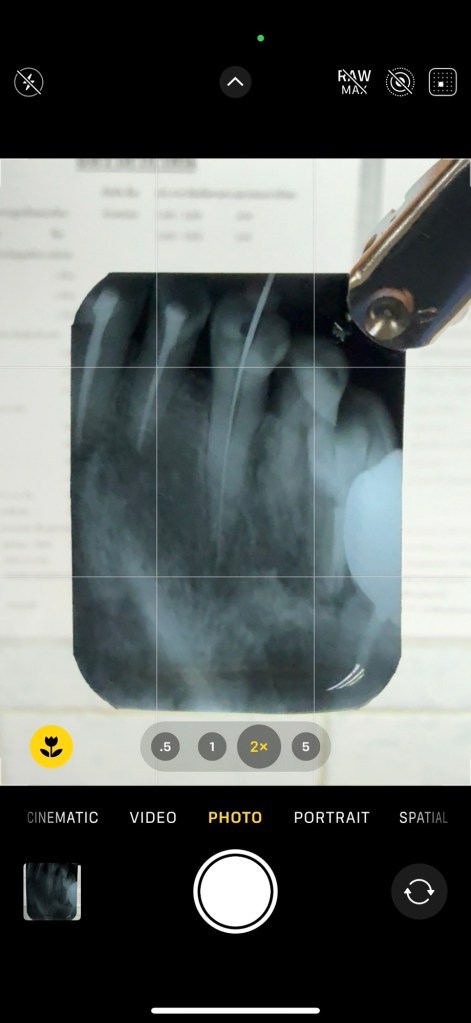

สิ่งแรกที่ต้องทำเลย หลัง Transfer data เสร็จ คือ การลองกล้องครับ

นี่คือ รูปจากกล้องรูปแรก

ลองใช้กล้องในที่ทำงาน

พบว่า ระยะที่ดีที่สุด คือ 2x ครับ

ระยะ 5x ไม่ค่อย work ถ้าใช้มือจับ (ต้องใช้ขาตั้งกล้อง)

ในส่วนของกล้อง โดยรวม iPhone 16 ไม่ต่างจาก 15 ครับ มันคล้ายกันมาก ซึ่งสอดคล้องกับ Score จากเวบที่ทดสอบ

ผลออกมาไม่ค่อยแตกต่างครับ

เช่น Dxomark ปกติถ้า Apple เปลี่ยนแปลงกล้องมากๆ อันดับ Dxomark จะเข้ามาที่ 2nd แต่ปีนี้หลุดไป 3rd

นั่นหมายความว่า ก่อนสิ้นปีนี้ iPhone 16PM จะถูกค่ายจีน เบียดตกจาก Top 5 แน่ๆ

ของค่ายนี้ เห็นได้ชัดว่า กล้อง 16PM ไม่ได้ต่างจาก 15PM อย่าง significant เลย

แต่ ถ้าลองวัดความรู้สึกจากการใช้งานจริง อาจเป็นอีกแบบ